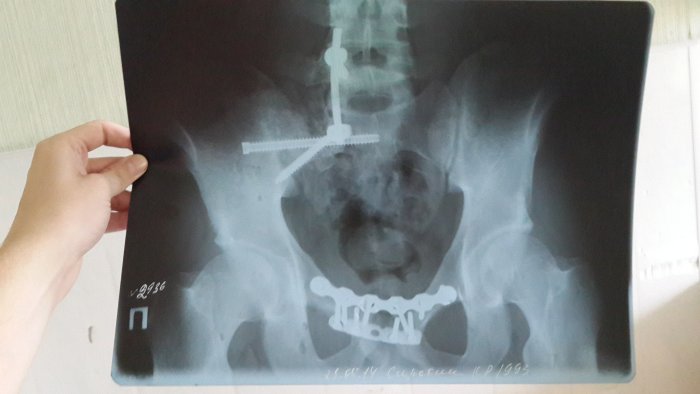

Свердловские судебные приставы взыскали полмиллиона рублей в счет компенсации морального вреда с первоуральского ООО «Геострой-монтаж» в пользу сотрудника общества. Мужчина, работавший электромонтажником, получил перелом позвоночника в результате падения на него некой конструкции, - сообщили в пресс-службе УФССП России по Свердловской области.